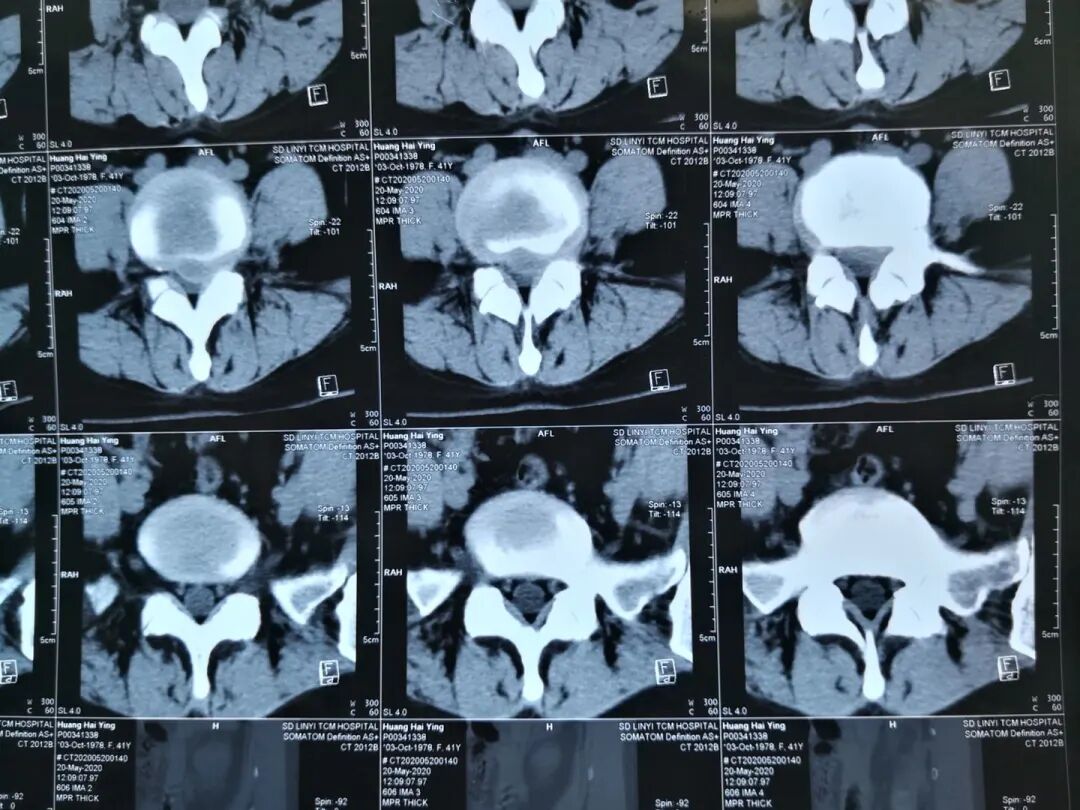

患者,黄某某,女,41岁,因左下肢疼痛伴麻木2年,加重半年入院;患者2年前无明显诱因出现左下肢疼痛,疼痛自臀部放射到小腿外侧,伴有足背部麻木感,活动后加重,于当地医院行CT检查示L4/5腰椎间盘突出,患者未予特殊治疗,近半年以来,感左下肢麻木疼痛加重,症状反复发作,行走后加重,影响日常生活,于院外的保守治疗无效。

查体: 腰椎生理曲度存在,腰椎屈伸活动稍受限,L4/5棘突间及 棘突旁压痛,伴左下肢放射痛,左侧足背部感觉减退,双下肢肌力正常,左路背伸肌力4级一,左下肢直腿抬高试验及加强试验阳性,双侧膝腿反射(+),双侧跟健反射(+),巴氏征(-),双下肢水梢毛细血管充盈良好。

图3:术前CT